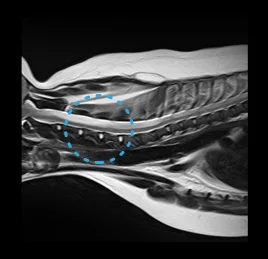

• 이도 염증 - 내/중/외이염

• 디스크 탈출증